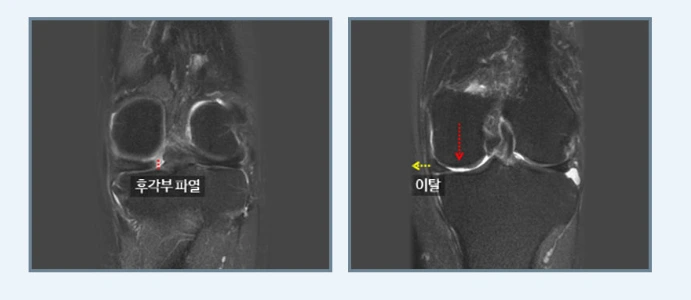

반월상연골판 손상

등산후무릎통증과 함께 무릎에서 소리가 난다면 반월상연골판 손상을 의심해야 합니다.

전영식 원장님“반월상연골판은 무릎관절에 가해지는 충격을 흡수하는 중요한 신체기관으로 만일 반월상연골이 찢어지거나 제거되어 제 기능이 없어진다면 무릎관절에는 정상보다 2~3배의 힘이 더 가중되어 관절연골 손상이 가속화되고 한 번 손상된 연골판은 자연 치유가 어려워 손상 부위가 점점 커져 조기 퇴행성관절염으로 이어지기도 합니다”라고 설명하며 반월상연골팜은 나이가 들면 작은 충격에도 쉽게 파열되기 때문에 등상 중 미끄러져 넘어지거나 급격한 방향전환으로도 부상이 생길 수 있다고 덧붙이십니다.

특히 평소 등산을 많이 하던 사람이 아닌 초보라면 내리막이 많은 산이라면 하산 시 무릎이 뒤틀리며 반월상연골판이 손상이 발생하기 쉬워 조심해야 합니다. 등산후무릎통증과 함께 무릎을 구부렸다 펼 때 뭔가 걸리는 느낌이나 조금만 무릎이 틀어지는 동작을 하면 삐걱대는 느낌이 들면 전문의를 찾아 정확한 진단을 받아야 하지요.

반월상연골판의 증상으로는 부종과 관절염의 통증, 걷거나 뛰거나 계단을 내려올 때 통증, 서있거나 가만히 있을 때, 잘 때 통증, 무릎을 구부리고 펼 때 걸리는 느낌, 관절 안에서 걸리는 느낌과 소리, 계단을 내려갈 때 갑자가 무릎에서 힘이 빠져 휘청거리는 느낌 등이 있어요.